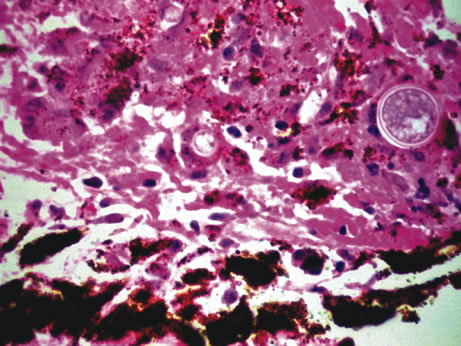

Infectious endophthalmitis refers to inflammation due to an infectious organism, usually bacterial, but it may also be caused by yeast or filamentous fungi. The vitreous is typically involved and supports the growth of the infectious intraocular organism. The reaction to the organism is usually severe and is characterized by abundant polymorphonuclear leukocyte infiltration. The infection is usually accompanied by tissue destruction due to the release of proteolytic enzymes in the severe inflammatory reaction. Uveal and retinal necrosis may occur during these infections. Endogenous endophthalmitis refers to hematogenous dissemination of organisms to the eye and can be seen in cases of septicemia from bacterial or fungal causes. The latter can be caused by Candida or Aspergillus species. Aspergillosis usually causes destructive choroidal inflammation (Fig. 24) with vascular occlusions. The infective organisms are found in the choriocapillaris or along the sub-RPE and sub-retinal space.126

Fig. 24. Aspergillus chorioretinitis. A. Hemorrhagic necrotizing retinitis and choroiditis are noted in a patient with disseminated aspergillosis (hemotoxylin-eosin ×60). B. Note the branching hypae of the organisms involving the retina and choroid (periodic acid–Schiff ×240).